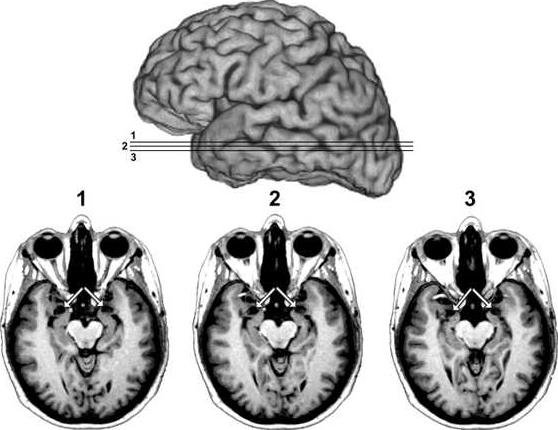

An undated image of a brain scan provided by the University of Iowa Department of Neurology, shows MRI scans of patient SM's brain. The arrows point to the amygdala, the region of the brain which SM is missing, as shown by the vacant black holes underneath the arrows. - photo by AP Photo/University of Iowa Department of Neurology